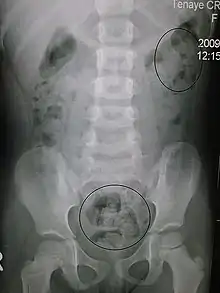

This image shows constipation in a young child as seen on X- ray.

In order to correctly manage neurogenic bowel dysfunction it is important to accurately diagnose it. This can be done by a variety of methods, the most commonly used would be taking a clinical history and carrying out physical examinations which may include: abdominal, neurological and rectal examinations. [16] Patients may use the Bristol Stool Chart to help them describe and characterise the morphological features of their stool, this is useful as it gives an indication of the transit time.[17] An objective method used to evaluate the motility of the colon and help with diagnosis is the colon transit time.[18] Another helpful test to diagnose this condition may be an abdominal X- ray as this can show the distribution of the faeces and show any abnormalities with the colon for example a megacolon.[13] Methods used for diagnosis may vary depending on if the patient is incontinent or constipated